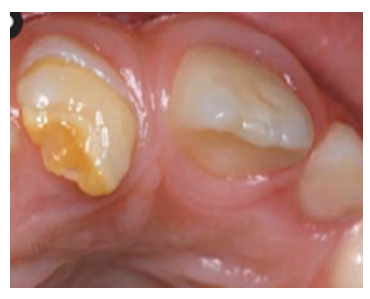

Faktori koji dovode do stvarnja gleđi slabijeg kvaliteta mogu da deluju sistemski, što znači da se radi o promenama u kompletnom organizmu zbog nekih trovanja(npr višak fluora, olovo, neki antibiotici ili drugi lekovi, poremećaji u metabolizmu), opštih oboljenja(virusne i bakterijske infekcije, poremećaji krvi, žutica i sl.) ili pak nedostatka sastojaka ishrane važnih za razvoj mineralizovanih tkiva(vitamin D i A, kalcijum i sl.). Dejstvo sistemskih faktora se ispoljava na više zuba i to na onim delovima zuba koji su se razvijali u periodu njihovog dejstva, pošto se svi zubi i njihovi delovi ne razvijaju istovremeno. Ostali delovi zuba, ako je faktor delovao samo u određenom vremenskom periodu, ostaju zdravi. Na osnovu položaja oštećenja može da se oderedi kada se i atak dogodio. Za razliku od ovih sistemskih razvojnih poremećaja, nasledni(genetski) poremećaji ne pokazuju specifičnu lokalizaciju veznu za određeni period razvoja zuba, već su nepravilno raspoređni po celoj površini krunice i najšeće na svim zubima.(slika 2.)